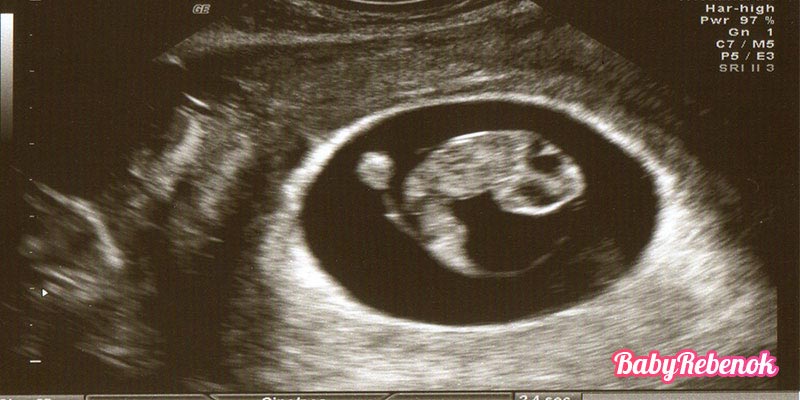

На 8 неделе не требуется проведения УЗИ, но многие мамочки его делают для собственного спокойствия, чтобы убедиться, что происходит с малышом, все ли с ним в порядке, а также исключить вероятность внематочной беременности. 8 неделя беременности – это срок, когда на УЗИ можно четко различить голову и туловище эмбриона, а также заметить формирование индивидуальных черт лица. Глаза все еще выглядят как 2 черные точки и располагаются не симметрично друг к другу, тем не менее, уже начинает свое формирование веко и реснички, и все более четко проступают очертания носа, губ и подбородка. Главным показателем правильного течения в развитии плода на этом сроке является количество сократительных движений сердечной мышцы малыша. В норме на 8 неделе беременности частота ударов составляет от 150 до 170 ударов в минуту.

Фото УЗИ на 8 неделе беременности